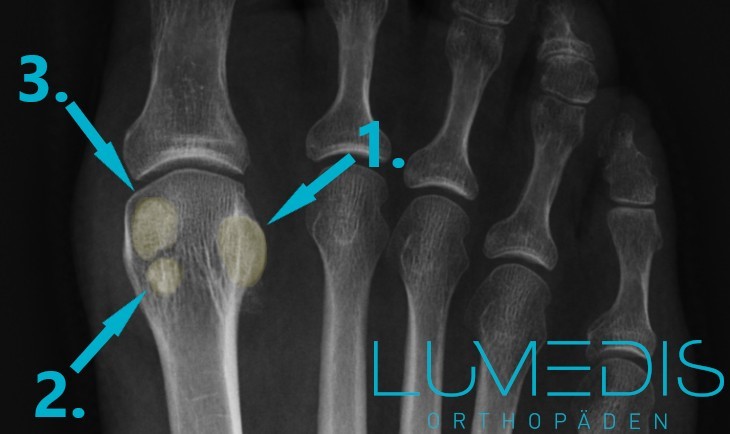

MRT mit Bruch/Fraktur des Sesambeins der Großzehe

Die türkisen Pfeile zeigen auf eine Entzündung des medialen (inneren) und lateralen (äußeren) Sesambeins.

Röntgenbild eines geteilten Sesambeins